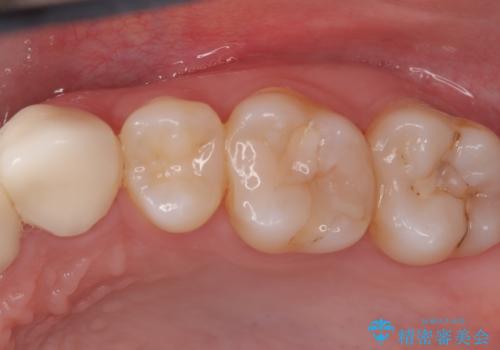

虫歯を治したい〈セラミック〉

- 虫歯の治療を希望されました。一番奥の歯は虫歯が深かったことから神経を部分的に残す治療法(生活歯髄療法)や神経の治療(根管治療)についても説明し、治療介入をしました。

材料の特性を説明し、材質はどちらもセラミック、手前の歯は部分的な詰め物、奥の歯は被せ物での修復となりました。

左上7番は治療前の神経の検査では正常の範囲内の値を示しました。虫歯を削っていったところ神経まで到達したため、神経を部分的に残す治療法を選択しました。その後痛み等症状が出ず、また、神経の反応も正常であったため、被せ物にしています。